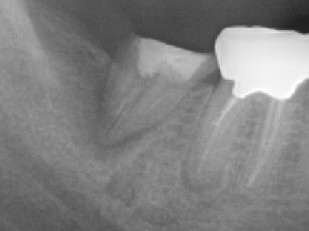

画像1

2本の歯が写っていますね。

向かって左側の歯(7番)はクラウンが無く、根っこの周りがボヤ〜っと黒っぽく写っています。

向かって右側の歯(6番)はクラウンが被っています。そして、2本ある(ように見える)根っこのうち、左側の根っこの先が少し黒くなっているように見えます。